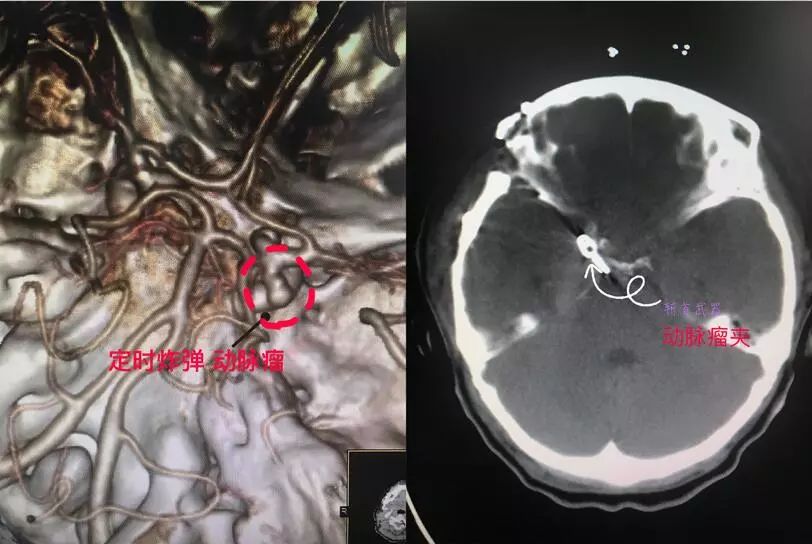

3、动脉瘤夹闭:

二、脑血管造影、颅内动脉支架、动脉瘤夹闭、栓塞,血管搭桥治疗烟雾病等缺血性脑血管病。脑出血及脑干出血的精准微创手术治疗。